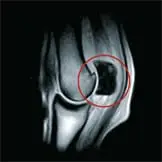

Die MRT-Untersuchung ermöglicht eine besonders detaillierte Darstellung von Weichteilstrukturen und Knochen, insbesondere im Bereich der Gliedmaßen. Besonders wertvoll ist sie für die Diagnostik im Hufbereich, da dort wichtige Strukturen wie die tiefe Beugesehne oder Schleimbeutel liegen, die mit anderen bildgebenden Verfahren nur schwer darstellbar sind.

Außerdem können Veränderungen im Knochenmark – sogenannte Knochenödeme – sichtbar gemacht werden. Diese Flüssigkeitsansammlungen im Knochen entstehen zum Beispiel bei Überlastung, Mikrofrakturen oder Entzündungen. Werden sie rechtzeitig erkannt, kann die Therapie gezielt angepasst werden, um schwerwiegendere Schäden wie Stressfrakturen oder chronische Lahmheiten zu vermeiden.